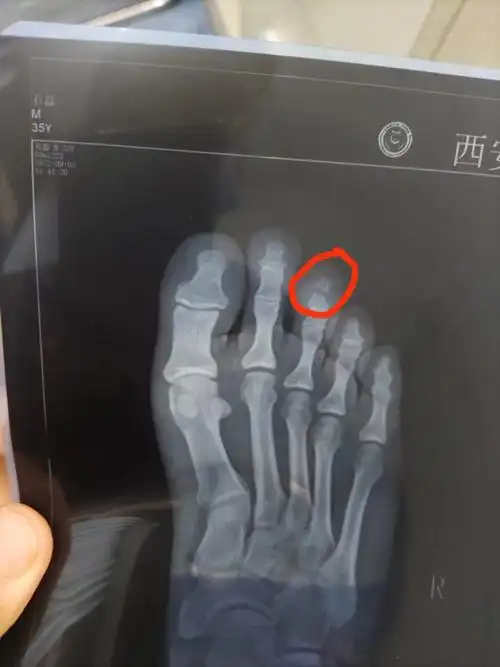

大脚趾两处骨折第41天

请有骨科的专家帮我看张片子,我在两个医院看的,一个医院说的大的脚趾

趾骨骨折20天对比

趾骨骨折经典案例